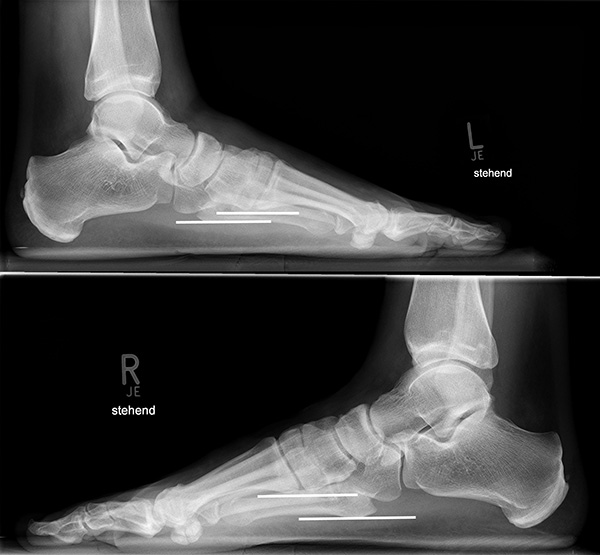

Standardisierte Röntgenaufnahmen des betroffenen Fußes, dorsoplantar (dp), streng seitlich sowie eine Schrägaufnahme werden angefertigt. Diese sollten möglichst unter Belastung angefertigt werden, da in den unbelasteten Aufnahmen insbesondere diskrete Veränderungen häufig nicht sicher zu erkennen sind.

Auf den dp-Aufnahmen sollte der mediale Rand der Metatarsale-2-Basis mit dem medialen Rand des Os cuneiforme intermedium eine homogene Linie ohne Stufenbildung bilden (Abb. 7+8). Außerdem ist auf den Abstand zwischen der Metatarsale-1- und -2-Basis zu achten. Dieser sollte nicht größer als 2 mm bzw. im Vergleich zur Gegenseite nicht mehr als 1 mm erweitert sein. In bis zu 90% der Fälle zeigt sich ein sogenanntes „Fleck sign“ (Abb. 9), ein knöchernes Fragment zwischen der Metararsale-1- und -2-Basis im Sinne eines knöchernen Ausrisses des Lisfranc-Ligaments an der Metatarsale-2-Basis 211936410. Oft liegen zusätzliche Frakturen der Metatarsalebasen oder der Tarsale vor, die ebenfalls identifiziert werden sollten. Bei jeder Mittelfußbasisfraktur sollte umgekehrt an eine Lisfranc-Verletzung gedacht werden.

In der Schrägaufnahme sollte der mediale Rand des Cuboids mit dem medialen Rand der Metatarsale-4-Basis eine homogene Linie bilden.

In der seitlichen Aufnahme ist auf Dislokationen und Subluxationen in den Tarsometatarsalgelenken sowie auf einen Verlust des Fußlängsgewölbes zu achten. Bei Instabilitäten des 1. Strahls bzw. Abflachung des Fußlängsgewölbes tritt in der Seitaufnahme die plantare Kontur des Os cuneiforme mediale tiefer im Vergleich zur Basis des Metatarsale 5. Darüber hinaus sollte die Cyma-Linie im Bereich des Chopartgelenkes in der Seitaufnahme eine harmonische S-förmige Linie bilden.

Insbesondere bei rein ligamentären, aber auch subtilen Verletzungen können belastete Vergleichsaufnahmen der unverletzten Gegenseite oder Streßaufnahmen des verletzten Fußes unter Bildwandlerkontrolle hilfreich sein 161129584 (Richter 2007).

Aber auch in den belasteten Röntgenaufnahmen sind subtile Frakturen und Luxationen oder rein ligamentäre Verletzungen oft nicht sicher darstellbar 7.